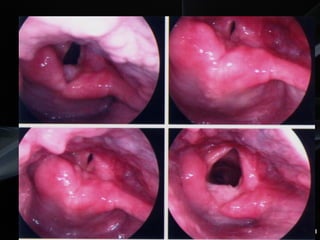

Cirurgia Endoscópica da Laringe

CIRURGIA ENDOSCÓPICA

Avanços técnicos

Laringoscópios

Óticas 0º/30º/70º

Material

microcirúrgico

Laser/CO2

Ressec. End. Laser

Indicações

Tumores Glóticos ou supraglóticos

Estágios I ou II

Leve/moderada diminuição da mobilidade

Ø fixação na comissura anterior

Pequena extensão supra e/ou subglótica

Ferris RL, Simental A. Operat Tech Otolaryngol – Head Neck Surg 2003;14(1):3-11.